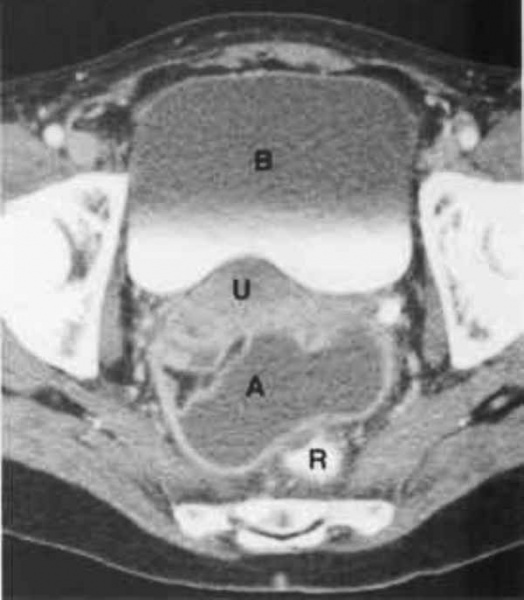

КТ диагностика тубоовариального абсцесса: Подходы и изображения

Раздел: Объективный взгляд